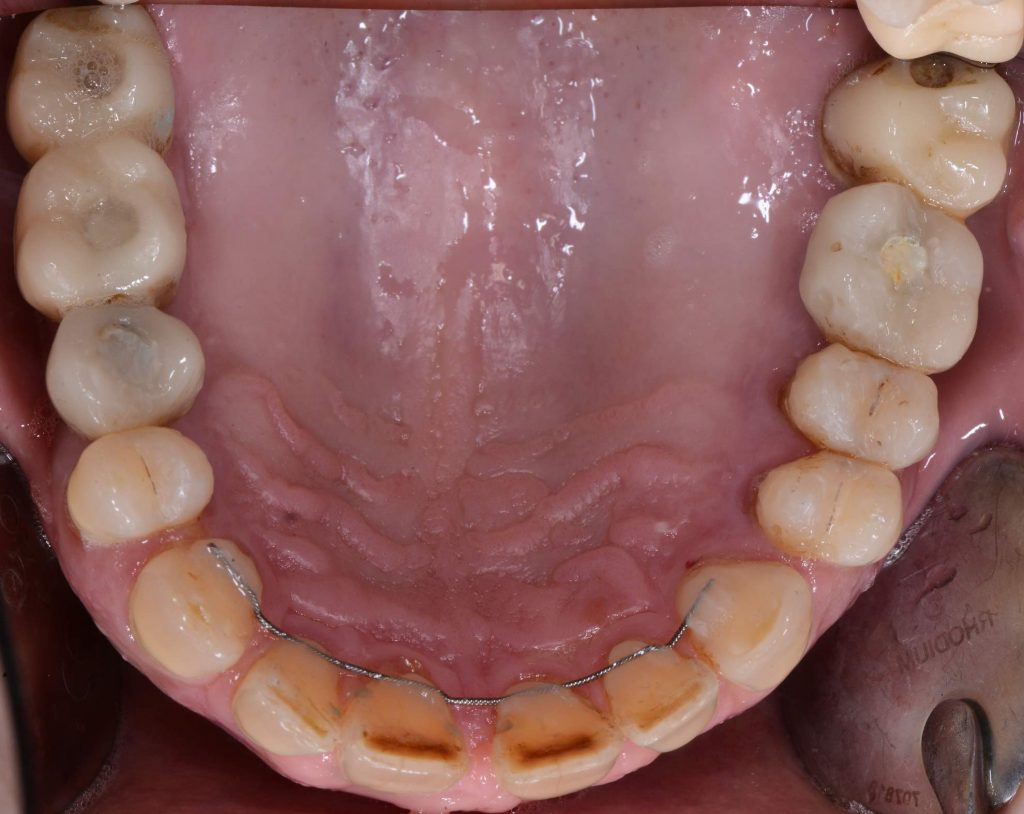

initial situation sinus lift cresta approach

initial situation occlusal view